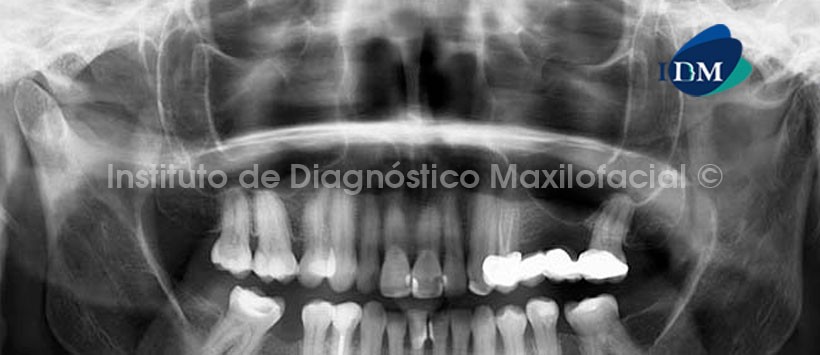

En la radiografía panorámica (Fig. 1) se observa una imagen radiolúcida de limites definidos y corticalizados proyectada en la zona sinfisiaria, en relación de cercanía con el periápice de las piezas 3.1, 4.1, 4.2, y 4.3 y con la basal mandibular, por otro lado se observan múltiples restauraciones coronales, la presencia de un puente protésico en el segundo cuadrante, la ausencia de multiples piezas dentarias y, como un hallazgo adicional, las calcificaciones a nivel de la cámara pulpar en las piezas posteriores de ambos maxilares.